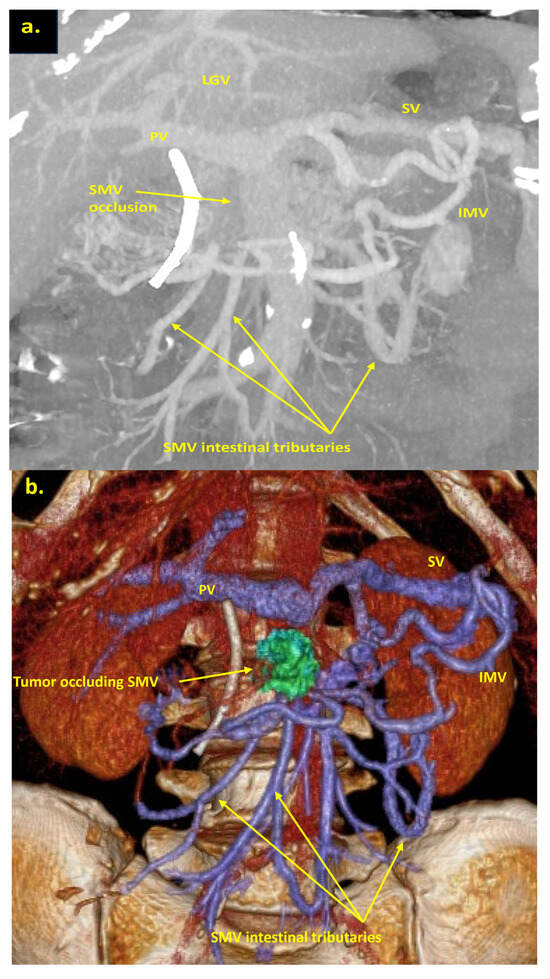

The combination of CT, MRI, PET/CT, and blood CA 19-9 was used as the best modality for the selection of candidates for radical surgery in patients with LA PDAC [11] by the evaluation of vascular involvement and distant metastases. Interpretation of the standardized digital images from the preoperative multiphase pancreatic MDCTs, MRIs, and PET/CTs (when available) of all 19 patients was independently performed by three abdominal image readers (PP, AD, EK). High-quality CT-based pancreatic protocol was the standard method of the anatomical resectability assessment with the analysis of four phases: native, arterial (pancreatic), portal venous, and delayed phases following high concentrated (350–400 mg/mL) non-ionic iodinated contrast media injection at the rate of 2.5–5.0 mL/s. CT examinations were performed between 2006 and 2024, using 32- to 256-detector scanners Philips Ingenuity, Philips iCT, GE optima CT 540, Philips Brilliance CT, Philips iCT, Toshiba Aqullion, and GE Revolution, with machine-specific image acquisition ranging from 0.625 to 3 mm axial slice thickness. Since 2008, 3D abdominal vein reconstructions have become useful and necessary components for decision-making on possible radical surgery for “low” pancreatic cancers with SMV thrombosis/involvement (Figure 1a–d). After ruling out the distant metastases, only patients with specific vein anatomy can be candidates for radical surgery. The mandatory anatomical conditions for the procedure were the following: (1) preserved SMV-SV confluence; (2) occluded SMV for any reason (tumor or thrombus); (3) well-developed inferior mesenteric vein (IMV) collaterals with dilated intestinal veins; (4) no right-sided vein collaterals (which will be sacrificed); and (5) no varices in the upper abdomen.

Figure 1.

Post-processing reconstructions of MDCT portal phase images for adenocarcinomas of the pancreatic uncinate process, associated with SMV occlusion, caused by its thrombosis and/or involvement. Three-dimensional maximum intensity projections (MIP) and volume-rendered (VR) imaging show preserved SMV-SV confluence, occluded SMV, well-developed IMV collaterals with dilated intestinal veins, and the absence of right-sided vein collaterals and varices. (a) Three-dimensional MIP reconstruction shows the dilated SMV tributaries, gastro-epiploic venous arcade (GEVA), left gastric (LGV), and inferior mesenteric veins (IMV) flowing into the splenic vein (SV); (b) three-dimensional MIP reconstruction. Dilated gastro-epiploic vein (GEV), and IMV anastomosing with the SV; (c) three-dimensional VR reconstruction. SMV is thrombosed and surrounded by the tumor; (d) three-dimensional VR reconstruction shows the dilated SMV tributaries and IMV flowing into the splenic vein (SV). The tumor shrank after chemotherapy, the SMV is occluded and the narrow left SMV is going along it. PV-portal vein. Abbreviations correspond to all the figures.

We used different post-processing CT techniques for the assessment of the peripancreatic vessels and collateral venous blood flow adequacy, such as shaded surface display, maximum intensity projection, and 3D volume-rendered (VR) reconstruction imaging. Now, when planning SMV resection with excision of all its tributaries for “low” pancreatic cancer, we consider CT-based 3D-VR reconstruction the best and most necessary option for the depiction of the collateral venous system. Compared to the other rendering CT techniques, VR is superior in delineating vessels, pancreatic parenchyma, the tumor, and adjacent structures (Figure 1a–d, Figure 5a,b, Figure 6a,b and Figure 7a,b,d) [43,44,45].